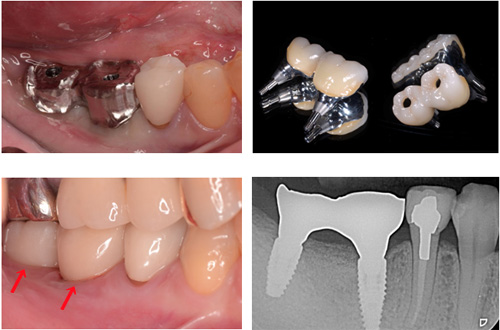

実際の治療 奥歯2本の症例

こちらの人工歯はセラモメタルクラウンですが、2本でトータル72万円でした

実際の治療 前歯1本

こちらの人工歯はジルコニアセラミッククラウンでトータル45万円でした

金額は2019年12月のものです